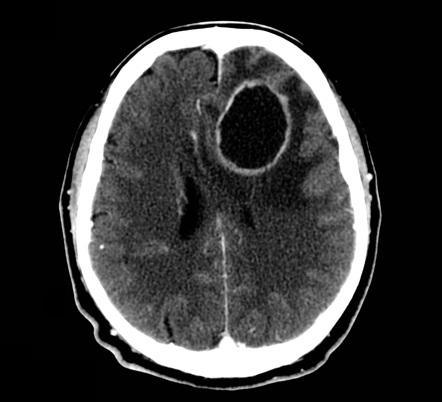

Frontal SOL